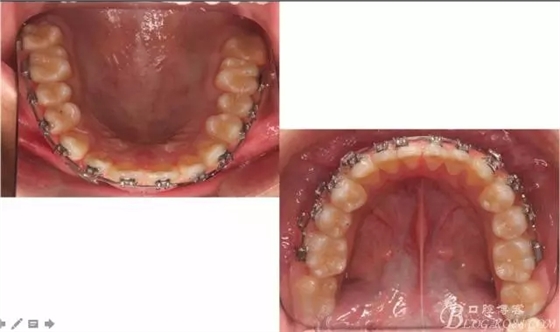

佩戴三個月的FR2, 效果奇佳!前牙基本達到淺覆蓋,淺覆合!接下來進入二期直絲弓固定正畸,排齊階段!

一晃快兩年了,我覺得關節(jié)重建及咬合穩(wěn)定,再加上患者的急迫愿望,我們拆除了矯正器。

尖牙關系中性,磨牙關系中性,咬合鎖結良好!